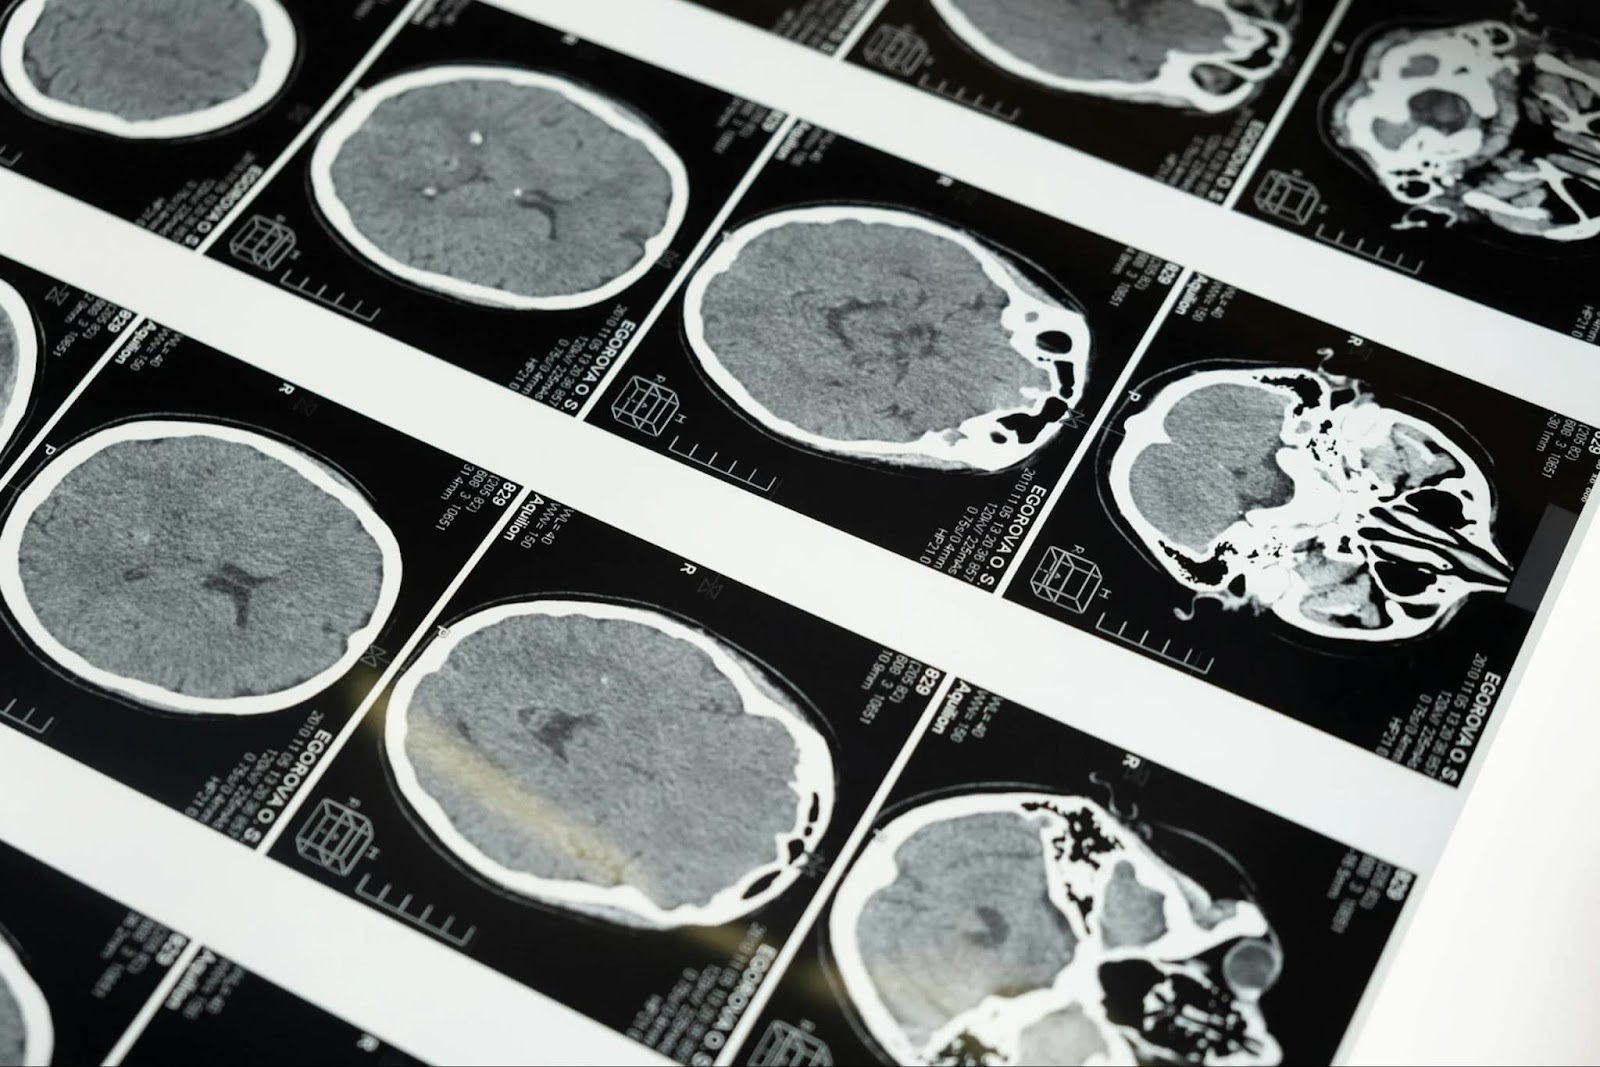

การแยกแยะทั้งสองประเภทนี้ทำได้ด้วยการตรวจ CT Scan สมอง ซึ่งเป็นเหตุผลที่ทำให้การมาโรงพยาบาลอย่างรวดเร็วเมื่อพบสัญญาณเตือน BE FAST มีความสำคัญอย่างยิ่ง เพื่อให้แพทย์สามารถวินิจฉัยและเลือกแผนการรักษาที่เหมาะสมได้อย่างถูกต้อง